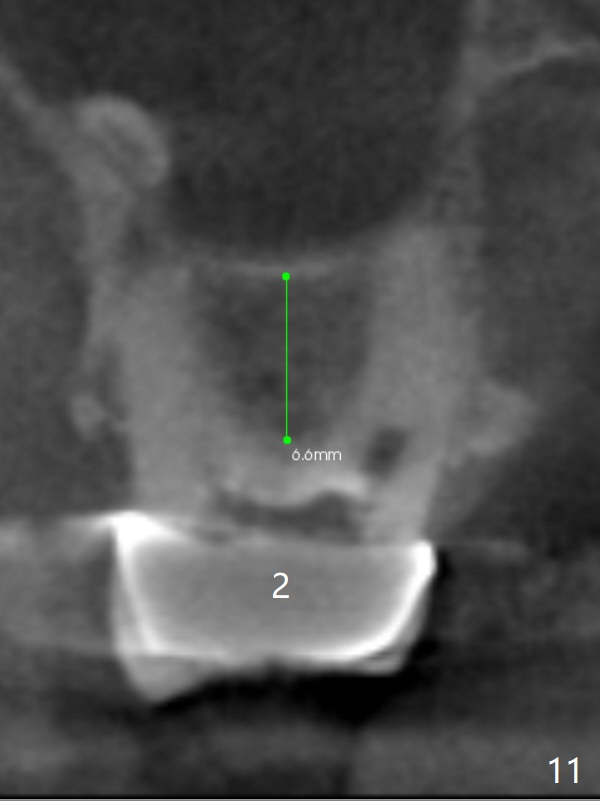

A 64-year-old man requests implant restoration after the upper FPD dislodges (Fig.1). The measurement of the septal height at #2 by PA (Fig.2) is not as precise as CBCT (Fig.11, taken 4 years earlier). There appears to be 2.8 mm bone apical to the tooth #4 (Fig.2); in contrast, the bone is more or less buccal and palatal to the root apex shown by CT (Fig.5). Furthermore CT more clearly shows apical lesions of the tooth #5 (Fig.3,4) than PA (Fig.2). In addition to pulpal test, RCT should be done for #5 prior to implant placement at #4.

Sinus lift at #2 is relatively easy because osteotomy is not to be done in a slope (Fig.3,11,12).